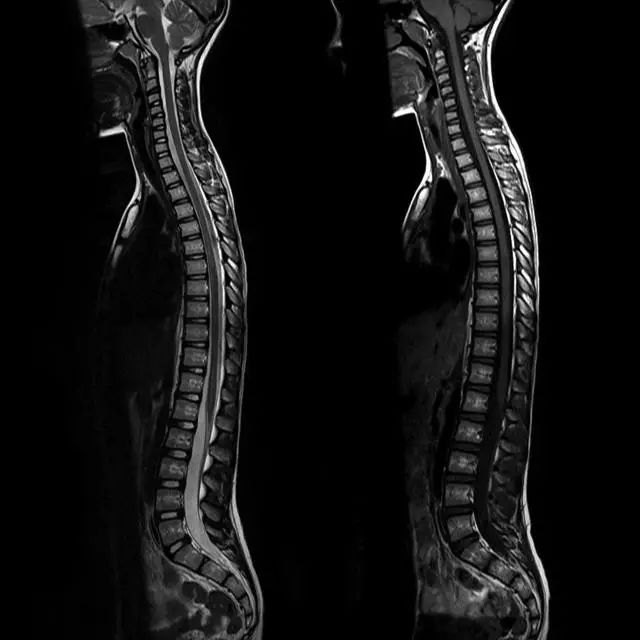

脊柱的MRI解剖

侧面观:可见颈、胸、腰、骶四个生理性弯曲,颈和腰曲凸向前,胸和骶曲凸向后。

颈椎前凸 20°- 40°,胸椎后凸 20°- 40°,腰椎前凸 30°- 50°,骶骨后凸倾斜。